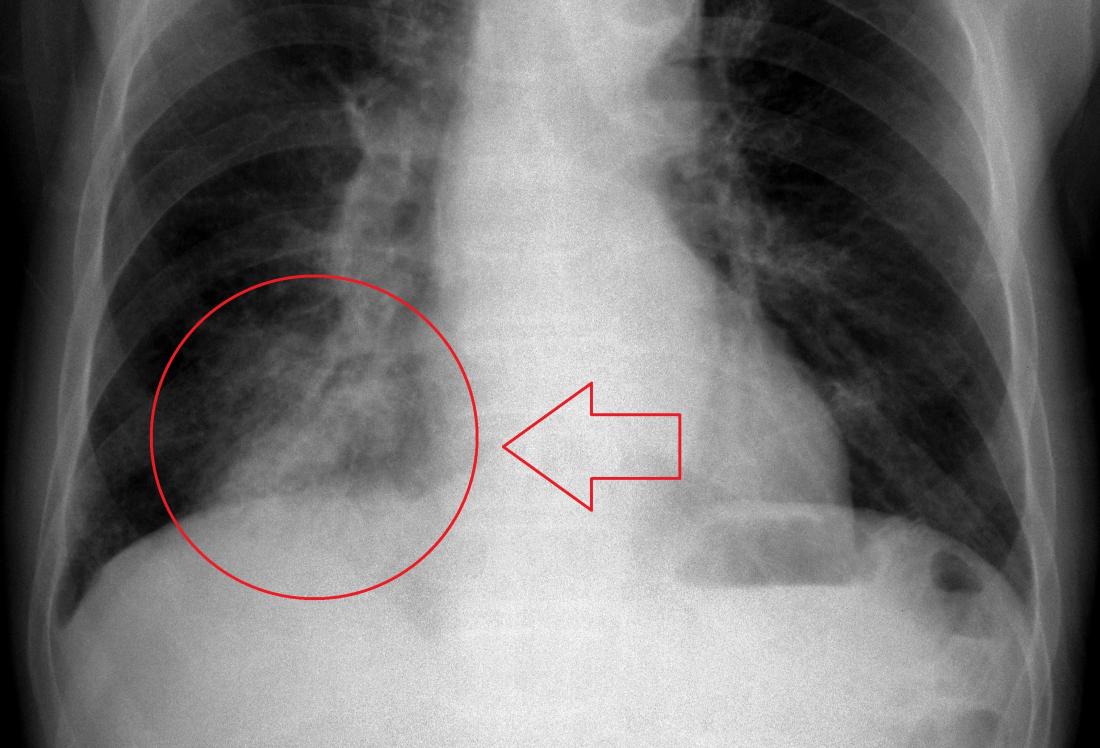

Сергей Авдеев: Да, отличия существенные. При COVID-19 практически всегда пневмония двусторонняя, расположена по периферии легких (под плевральной оболочкой). На начальных этапах она имеет вид, как говорят рентгенологи, «матового стекла». При прогрессировании изменения становятся более плотными и распространенными. А затем происходит фаза обратного развития — уменьшение размера и плотности легочных инфильтратов.

Если коротко, то при COVID-19 пневмония — двусторонняя, локализация — периферическая. Микоплазменные пневмонии чаще односторонние. Встречаются и двусторонние, однако в этом случае томографические снимки отличаются, изменения в легких иные.

Наши рентгенологи, описывая снимки легких при ковидных пневмониях, употребляют такие термины, как «булыжная мостовая», симптом «матового стекла». Именно так выглядят поражения

Одно из главных отличий вирусной пневмонии от бактериальной – быстротечность. Ковидное воспаление легких протекает стремительно и агрессивно

От «матового стекла» к «булыжной мостовой»

На раннем этапе заболевания, по словам врача, определить вирусную пневмонию можно только с помощью компьютерной томографии. Но если процесс уже достаточно распространен, врачи могут распознать вирусное воспаление легких и с помощью рентгенографии.

КТ на ранней стадии позволяет увидеть те изменения, которые называются синдромом «матового стекла». На снимке видно, что альвеолы как бы затянуты «дымкой». Если бактериальная пневмония проявляется в виде участков уплотнения, очаговых теней, то здесь легкая «дымка» окутывает все ткани альвеол.

Более тяжелые стадии вирусной пневмонии на рентгеновском снимке напоминают, по словам специалиста, «булыжную мостовую».